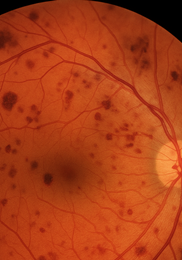

• 당뇨망막병증 – 모세혈관 누출로 혈액 성분이 유리체로 스며들며 거미줄 모양 혼탁이 나타납니다.

비문증 치료방법-비문증 원인